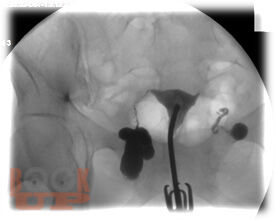

В пособии представлены данные об этиологии, современных методах диагностики и лечения бесплодия в браке. Подробно изложен алгоритм обследования супружеской пары на различных этапах постановки диагноза, тактика ведения пациенток. В результате использования учебного пособия студенты могут овладеть следующими компетенциями: ОПК 8, 11, 12; ПК 1, 5, 6, 8, 9, 10. Предназначено для использования в учебном процессе студентов старших курсов по специальностям: «Лечебное дело», «Педиатрия», «Медико-профилактическое дело».